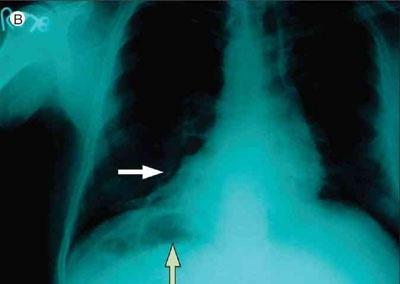

胸部x片示右位心(白色箭头,胃泡位于右膈下方(绿色箭头)c.

胸片表现包括外高内低的弧形影及肋膈角变钝;支气管血管纹理消失;以及